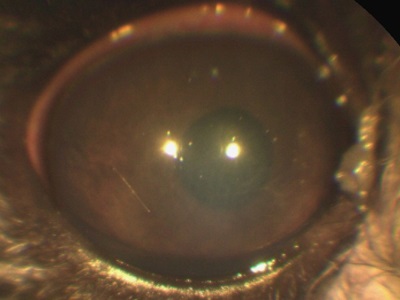

Atunci când diferite defecte ale corneei (eroziune, ulcer, traumatisme), creează edem, îngroșarea corneei, datorită cărora devine alb (opac).

defecte corneene apar, atât din cauza traumei de factori externi, și fără ele. Genele patologici, pleoape volvulus (parțială și completă), keratoconjunctivita sicca, toate acestea conduc la o leziune a corneei (eroziuni ale corneei sau ulcere).

Este important să distingem aceste stări patologice, ca și tratamentul eroziuni, ulcere și leziuni datorate diferitelor motive diferite. Oftalmolog specialist cu experiență suficientă și echipament specializat pentru a ajuta la identificarea bolii, și cauza algoritmului de acțiune.

Cheratita (inflamarea corneei) la câini și pisici, de asemenea, dat o culoare albă din cauza umflarea, impregnează celulele corneene ale sistemului imunitar, vasele de sânge germinare. Keratită pot apărea datorită infecții, tulburări ale sistemului imunitar, pleoape sau gene traumatizării constante ale corneei și așa mai departe.